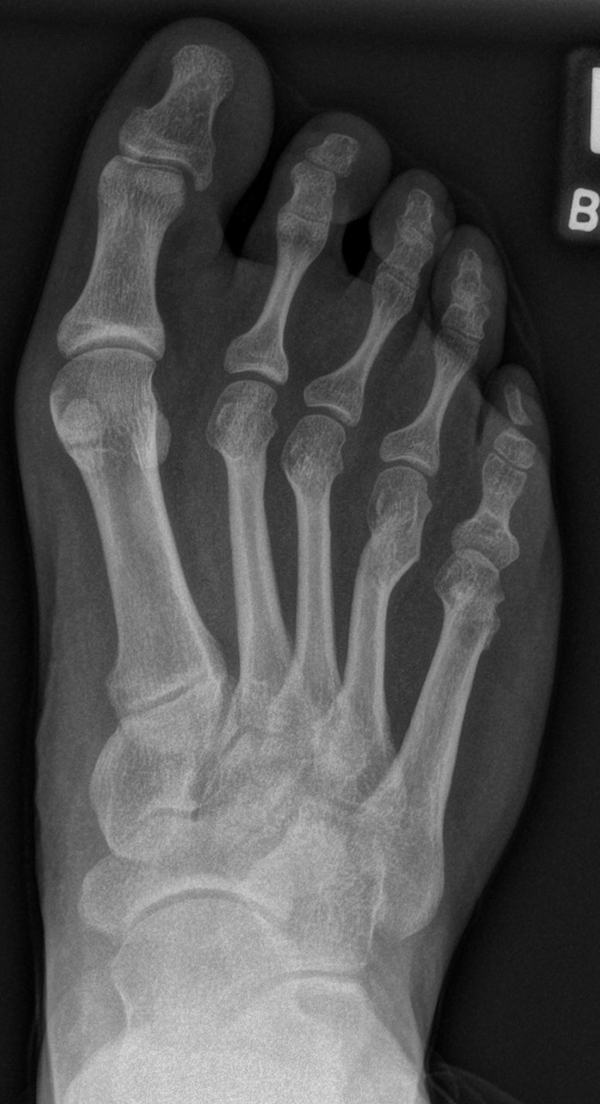

In der Regel bestehen aktive Wachstumsfugen bei Mädchen bis zum 12. und bei Jungen bis zum 14. Lebensjahr, mit Abweichungen von einem Jahr nach unten und nach oben. Präzise Informationen unter anderem darüber gibt das präoperative Röntgenbild (Abb. 2).

Abb. 2 a-c: offene Wachstumsfugen MT I Basis und Zehen (a), teilweise geöffnete Wachstumsfugen (b) und geschlossene Wachstumsfugen (c).

Zum Lesen der Bildbeschreibung und zur Vollansicht bitte die Bilder anklicken. Bilder: A. Helmers.